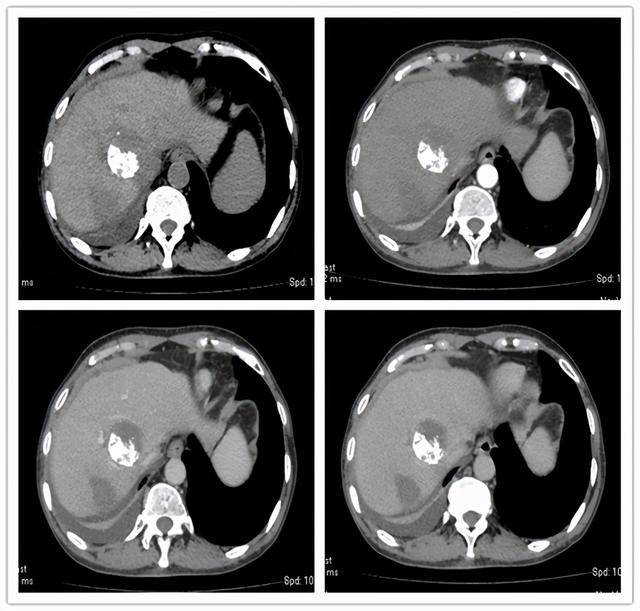

肝硬化和肝癌的ct图片

肝硬化结节癌变的早期影像诊断影像天地

肝脏疾病的ct表现

9.11腹部增强ct:肝右叶弥漫性肝癌

肝硬化肝癌的增强ct图像

肝癌:增强ct,典型"快进快出".